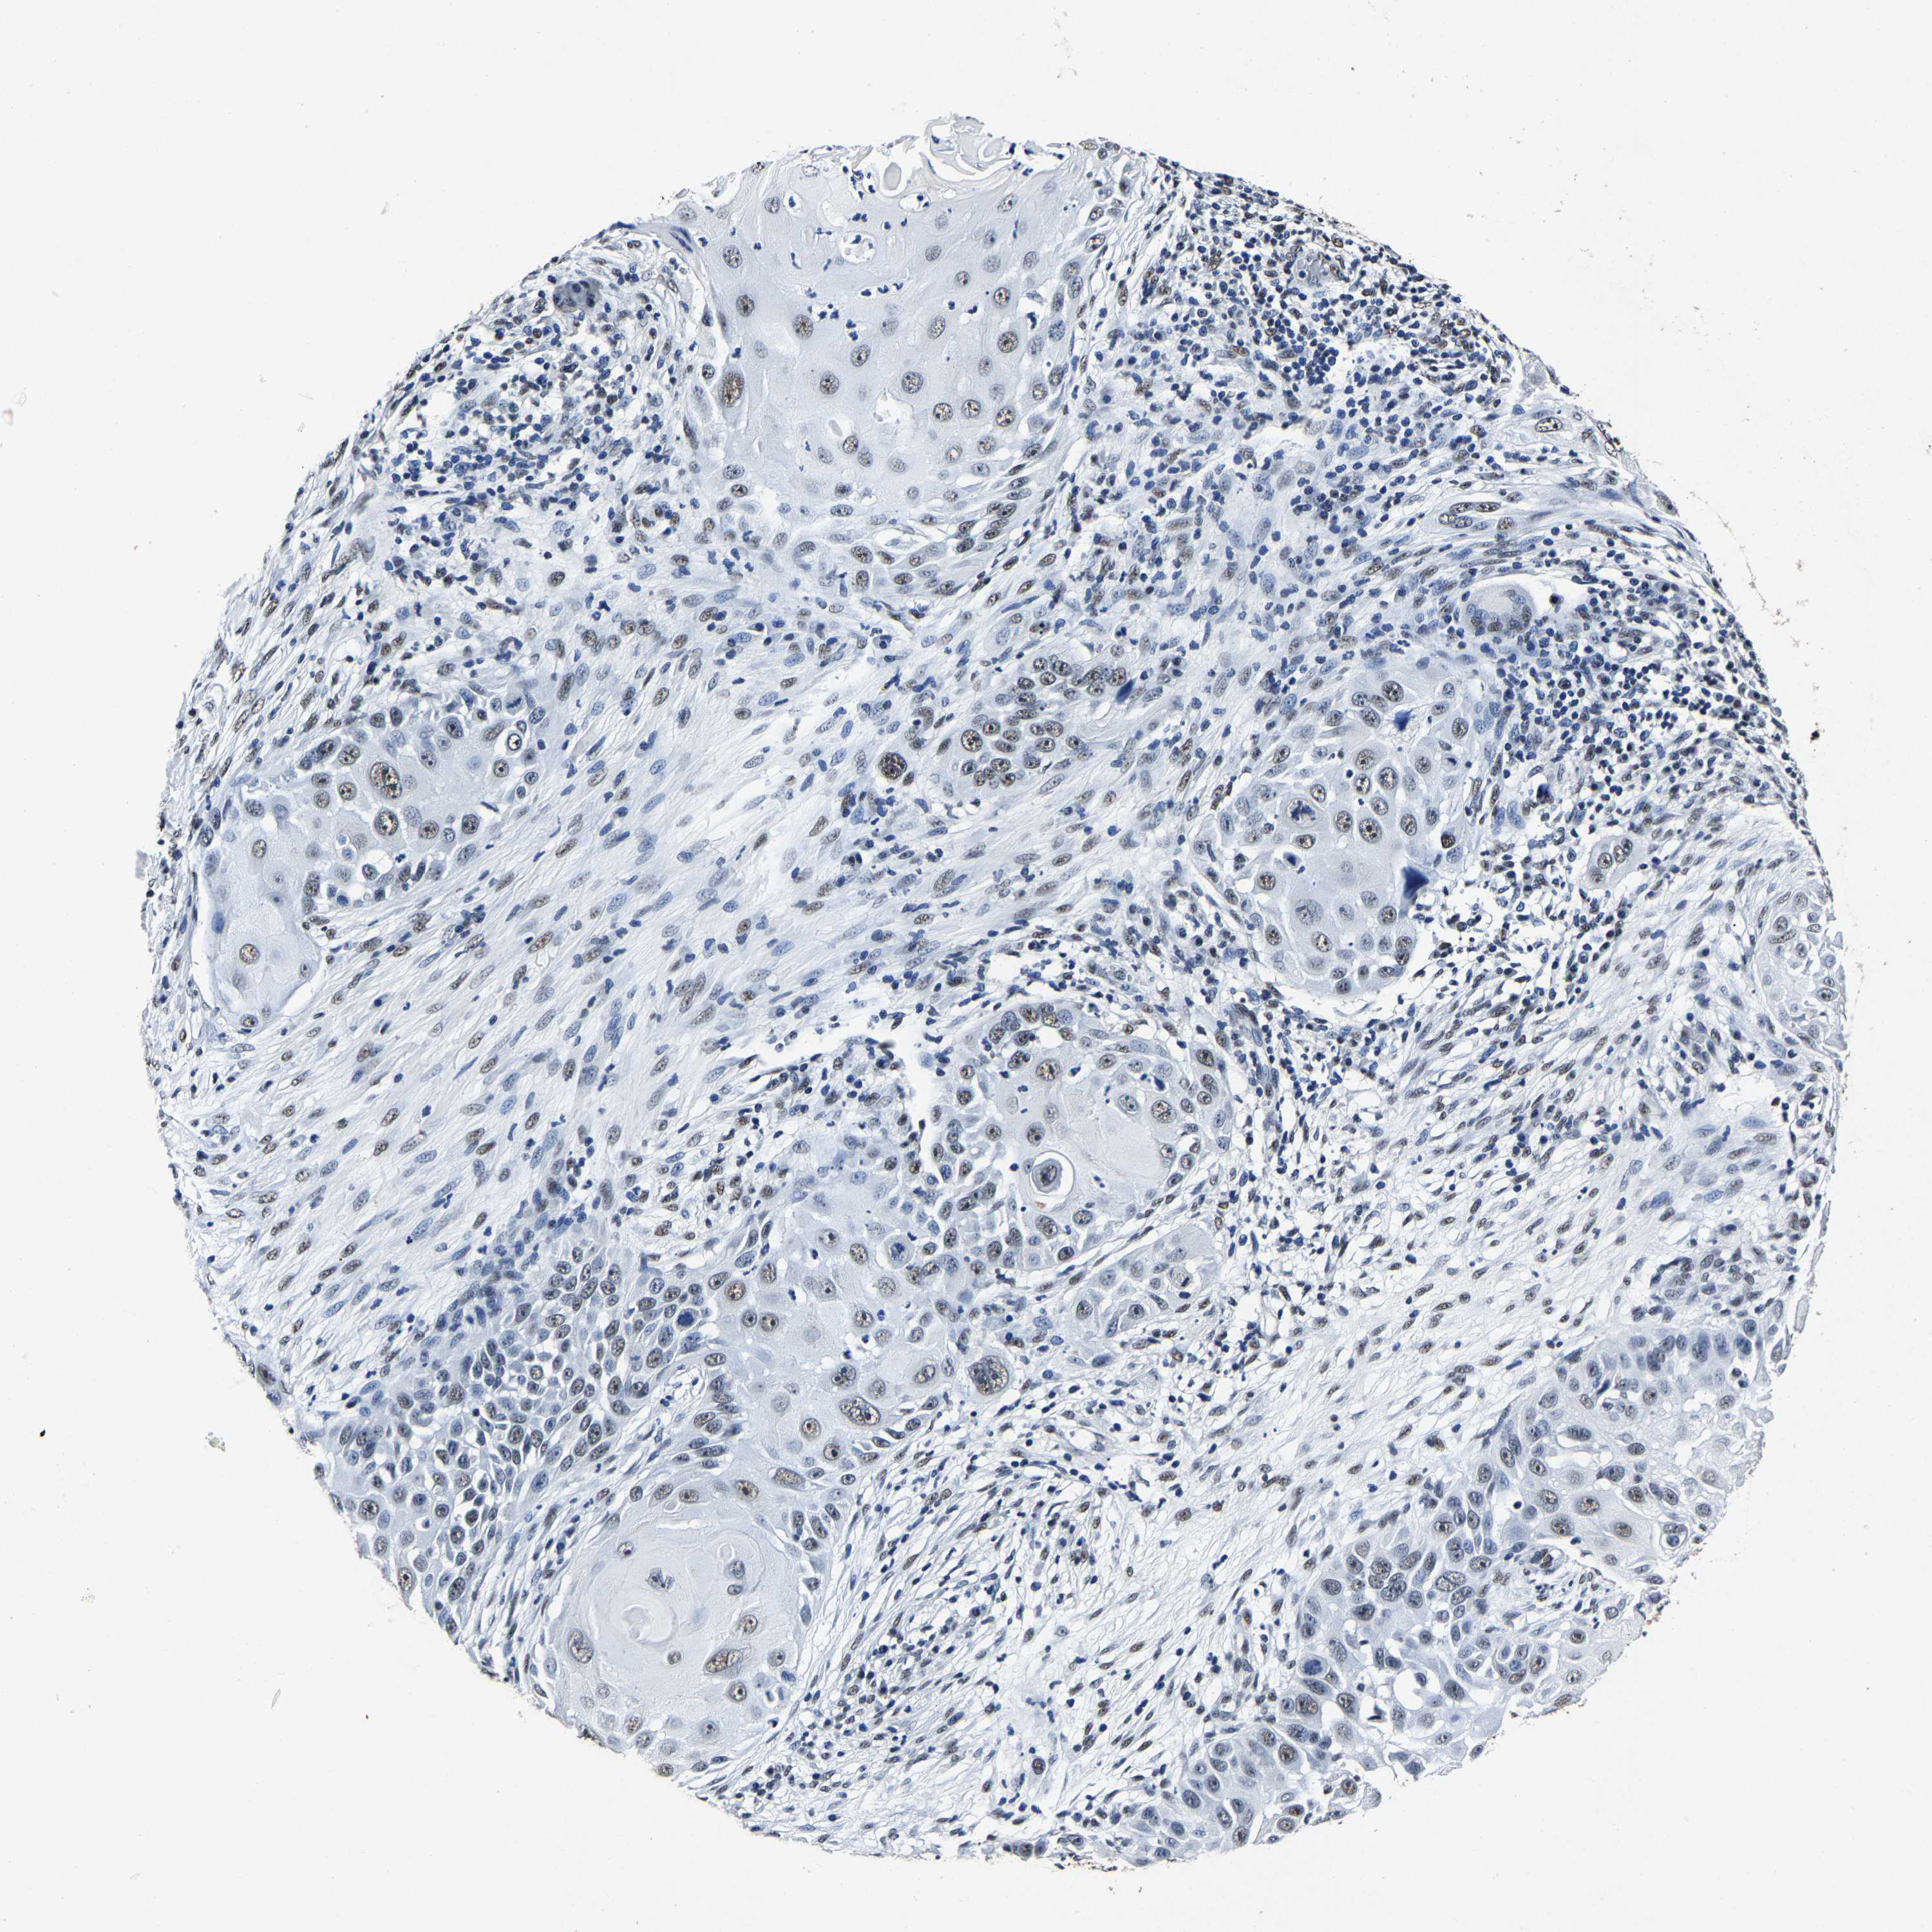

CANCER SKIN CANCER Show tissue menu

Basal cell and squamous cell cancer

SKIN CANCER - Protein expressioni

Antibody HPA020448

Staining

Medium

Intensity

Weak

Quantity

<25%

Location

None

Squamous cell carcinoma, NOS